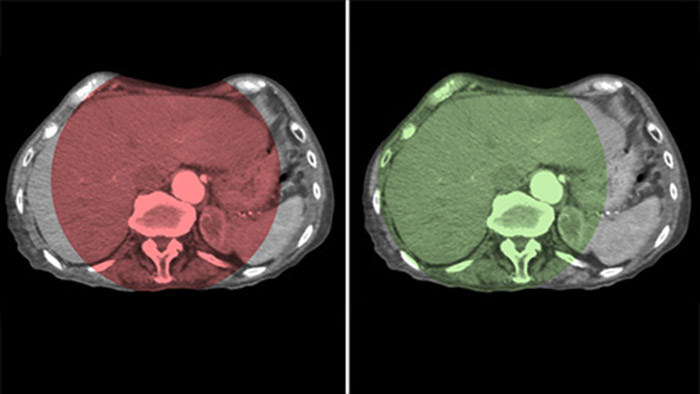

La fonction CBCT double affichage permet l’acquisition 3D d’une phase artérielle pour visualiser les structures vasculaires et d’une phase post-artérielle (phase retardée) pour visualiser l’accumulation du produit de contraste, en une seule étape automatique.5

Le double affichage permet la visualisation simultanée de deux ensembles de données CBCT. La phase artérielle et la phase retardée s’affichent l’une à côté de l’autre ou dans une seule vue fusionnée superposée.